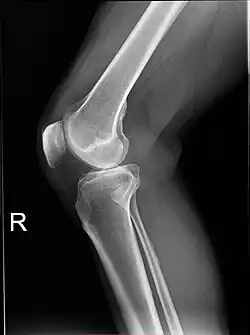

Projectional radiographs

Projectional radiography is the practice of producing two-dimensional images using X-ray radiation. Bones contain a high concentration of calcium, which, due to its relatively high atomic number, absorbs X-rays efficiently. This reduces the amount of X-rays reaching the detector in the shadow of the bones, making them clearly visible on the radiograph. The lungs and trapped gas also show up clearly because of lower absorption compared to tissue, while differences between tissue types are harder to see.[115]

Projectional radiographs are useful in the detection of pathology of the skeletal system as well as for detecting some disease processes in soft tissue. Some notable examples are the very common chest X-ray, which can be used to identify lung diseases such as pneumonia, lung cancer, or pulmonary edema, and the abdominal x-ray, which can detect bowel (or intestinal) obstruction, free air (from visceral perforations), and free fluid (in ascites). X-rays may also be used to detect pathology such as gallstones (which are rarely radiopaque) or kidney stones which are often (but not always) visible. Traditional plain X-rays are less useful in the imaging of soft tissues such as the brain or muscle. One area where projectional radiographs are used extensively is in evaluating how an orthopedic implant, such as a knee, hip or shoulder replacement, is situated in the body with respect to the surrounding bone. This can be assessed in two dimensions from plain radiographs, or it can be assessed in three dimensions if a technique called '2D to 3D registration' is used. This technique purportedly negates projection errors associated with evaluating implant position from plain radiographs.[116]